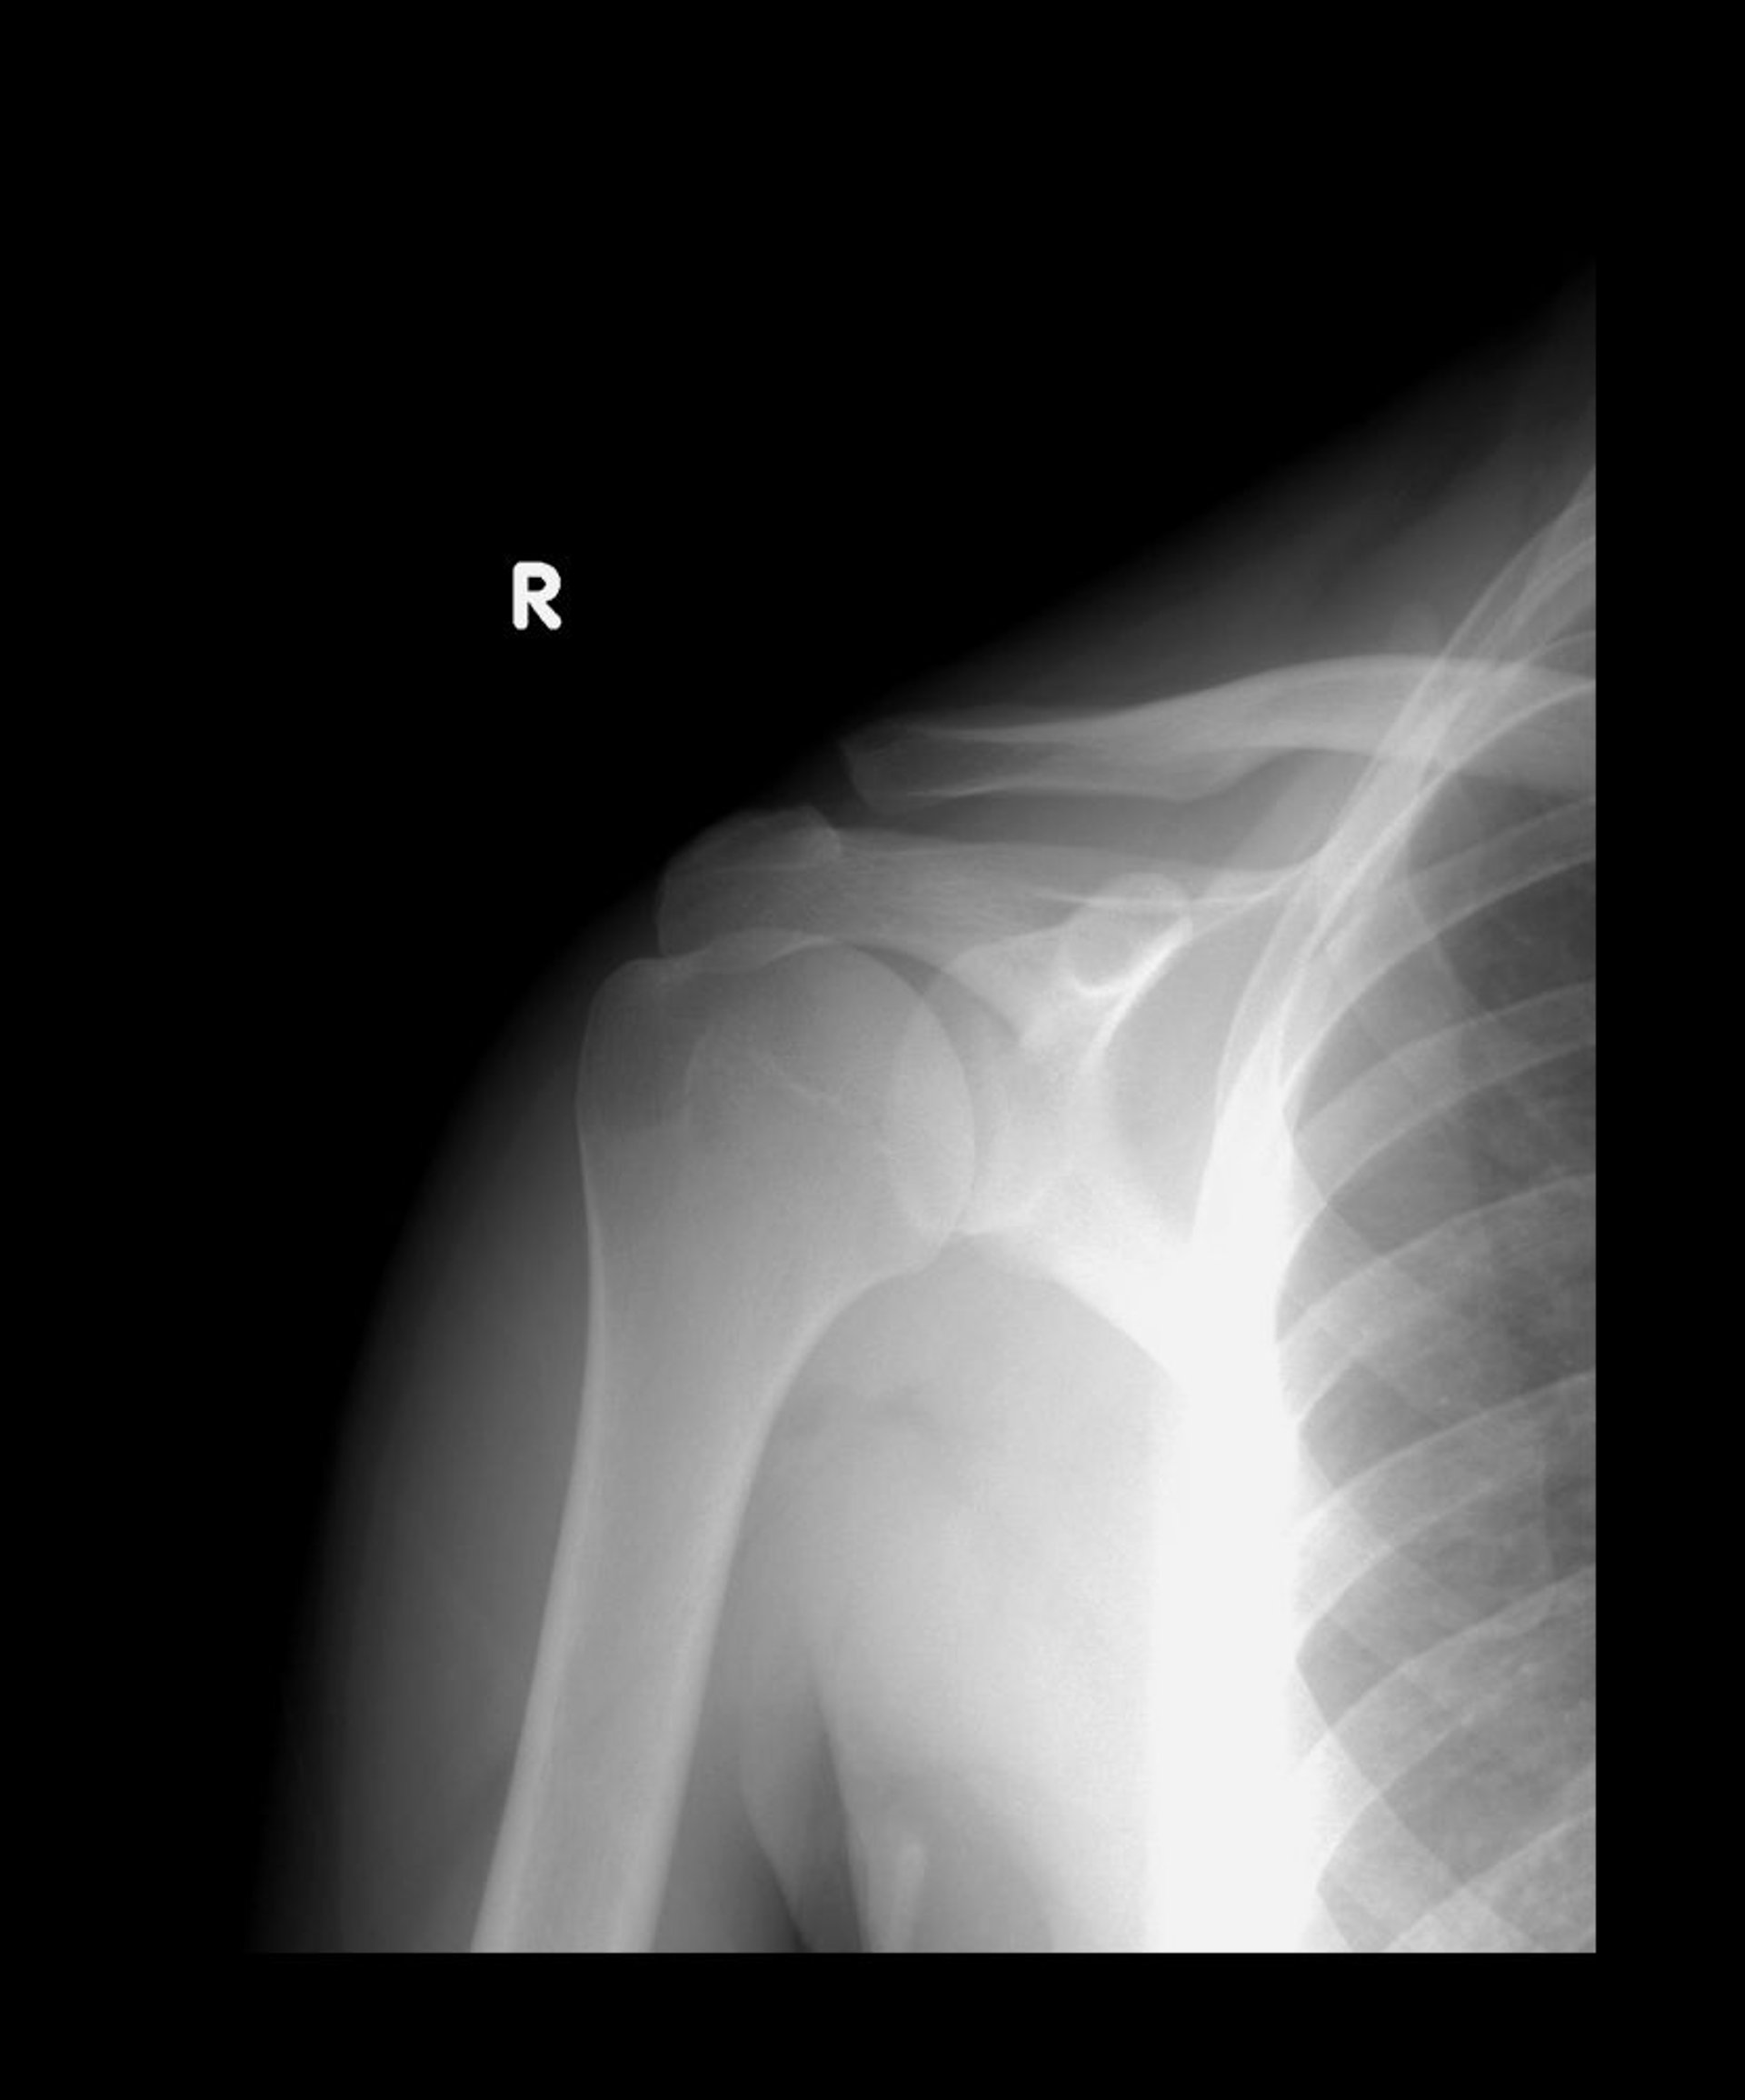

Растяжения связок акромиально-ключичного сустава

Как правило, нижние концы акромиального и ключичного сустава совмещены. На этом рентген-снимке, ключица смещена вверх, но 2 кости все еще перекрывают друг друга, что позволяет предположить подвывих II-го типа.